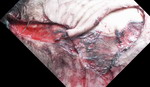

| Podbiegnięcia krwawe (sugillationes): powstają w momencie wynaczynienia się krwi z przerwanych naczyń krwionośnych do otaczających tkanek miękkich, przy utrzymanym krążeniu pod dostatecznym ciśnieniem. Tak więc nie dotyczą one tylko tkanki podskórnej ale także narządów wewnętrznych, takich jak mięśnie, wątroba, płuca itp. Powstają od zadziałania narzędzia twardego, tępego/tępokrawędzistego. Częstym problemem jest wyróżnienie podbiegnięć krwawych w tkance podskórnej w obrębie dobrze wysyconych plam pośmiertnych. W przypadku, krótkiego czasu jaki upłynął od zgonu (1-2 dni) w momencie nacięcia skóry w badanym miejscu, w przypadku plam pośmiertnych widoczna krew będzie wypływać jedynie z przeciętych naczyń krwionośnych (będzie można ją zetrzeć, natomiast podbiegnięcie krwawe nie znika pomimo przecierania. Jednakże wraz z upływem czasu dochodzi do przesiąkania krwi przez ścianę naczyń i podbarwiania okolicznych tkanek co w dużej mierze uniemożliwia makroskopowe odróżnienie zmian przeżyciowych od pośmiertnych, pomocne mogą być badania histopatologiczne. Kształt podbiegnięcia krwawego może być pomocny w identyfikacji narzędzia. I tak np. pasmowate zasinienia mogą odpowiadać pałce, kijowi itp. W przypadku uderzenia płaskim przedmiotem (deska, pasek) obrażenie może przybrać kształć dwóch równoległych pasm zasinienia biegnących w pewnej odległości od siebie, ta odległość w przybliżeniu odpowiada szerokości narzędzia co może być pomocne przy jego identyfikacji. Są pewne lokalizacja na ciele gdzie podbiegnięcie krwawe może sugerować obrażenia wewnętrzne. Np. zasinienie okolicy oczodołu (tzw. siniec okularowy) może wskazywać na złamanie przedniego dołu czaszki. Zasinienie w okolicy zausznej, na wysokości wyrostka sutkowatego wskazuje na złamanie podstawy czaszki. |

| Rany tłuczone (vulnera contusa): powstają w momencie przerwania ciągłości przynajmniej całej grubości skóry w wyniku zadziałania narzędzia twardego, tępego/tępokrawędzistego. Zazwyczaj mają kształt nieregularny z odgałęzieniam lub nieregularny. Brzegi ran są nierówne, otarte z naskórka, w dnie mogą być widoczne „mostki tkankowe” – czyli włókna tkankowe biegnące w poprzek osi długiej rany. W miejscach gdzie skóra przylega bezpośrednio do kości (czaszki, łokcie, kolna) w momencie urazu może ona równo „pęknąć”, imitując ranę ciętą, w biegunach rany jednak można się zwykle dopatrzyć mostków łącznotkankowych. Kształt ran tłuczonych, a zwłaszcza wygląd ich brzegów może odwzorowywać kształt narzędzi. Np. kształt litery „L” mają rany zadane narzędziem zakończonym narożnikiem (młotek, deska itp.). W przypadku uderzenia np. łomem możliwe że brzegi rany będę posiadały regularne głębsze otarcia naskórka odpowiadające gwintowi lub wzorowi na trzonku. Stwierdzenie podbiegnięcia krwawego w okolicy rany dowodzi jej zażywciowości. |